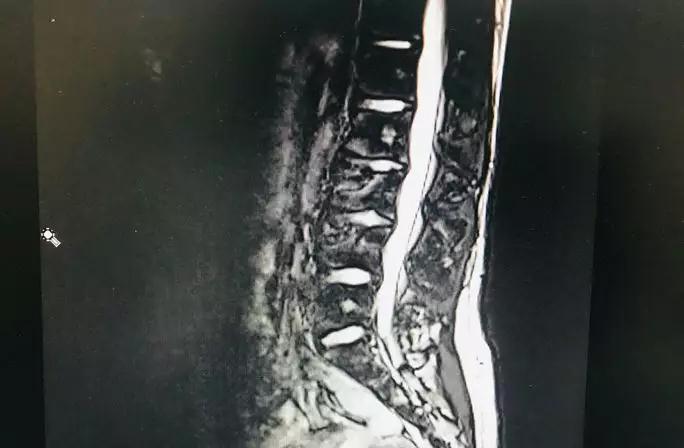

CT及MR检查

影像学上,发现部分椎体的前缘已经出现了楔形改变,且椎体出现了骨质疏松、分节、局部密度增高等表现,椎体形态不规则,正常骺板与椎体间的透明线不规则增宽。经过深圳市中医院骨伤科曹亚飞主任、李亨博士诊治后,确诊为休门氏病,经治疗后小琪的症状已经明显的缓解,又可以挺胸抬头的去上学了。